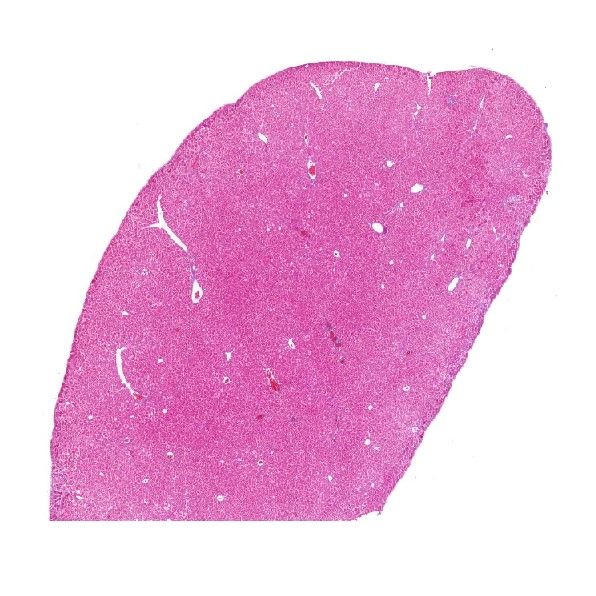

肝纖維化組織Masson染色

Masson染色